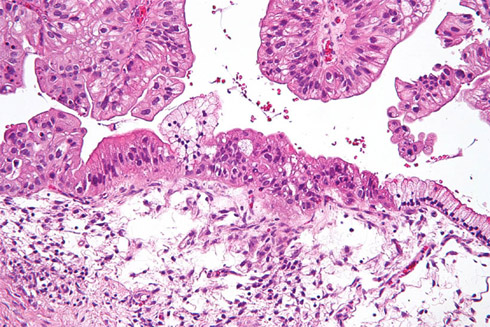

Micrografía de aumento intermedio de un tumor de ovario mucinoso de bajo potencial maligno (LMP). Tinción H&E. La micrografía muestra: epitelio mucinoso simple (derecha) y epitelio mucinoso pseudoestratificado (izquierda – diagnóstico de un tumor LMP). En la parte superior de la imagen se ve el epitelio en una arquitectura similar a una fronda. Foto: Wikipedia – CC BY-SA 3.0